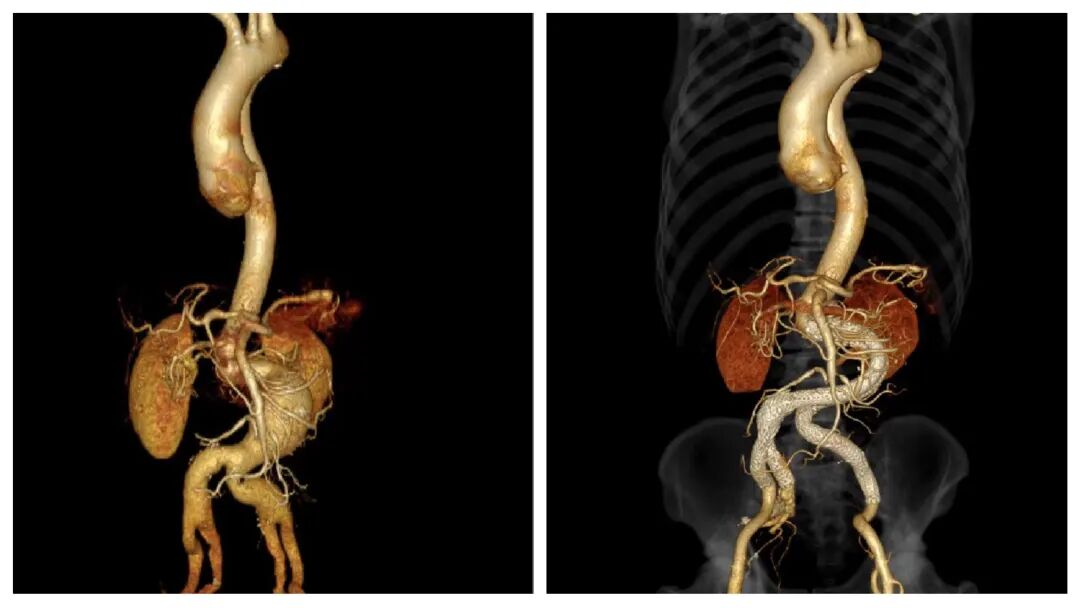

▲术前术后CTA对比

8月3日,该院介入血管科于黎明主任团队为索叔做了腹主动脉及双髂动脉DSA+腹主动脉覆膜支架腔内隔绝术+双髂动脉覆膜支架腔内隔绝术+右髂内动脉支架植入术。

经进一步检查,索叔被确诊为腹主动脉瘤,双侧髂动脉瘤。